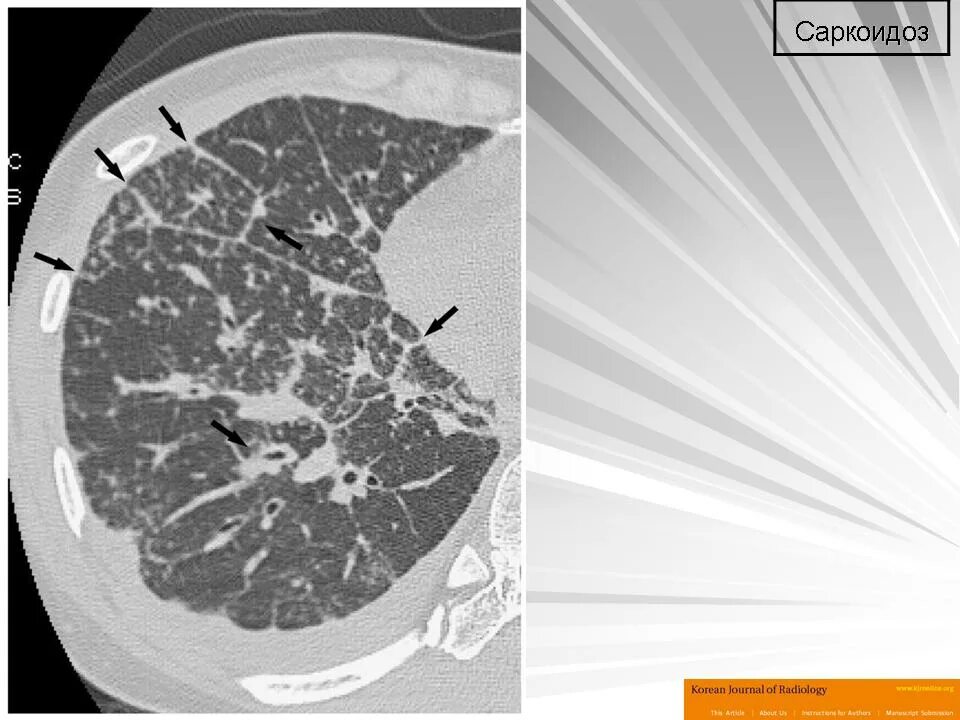

Саркоидоз 1